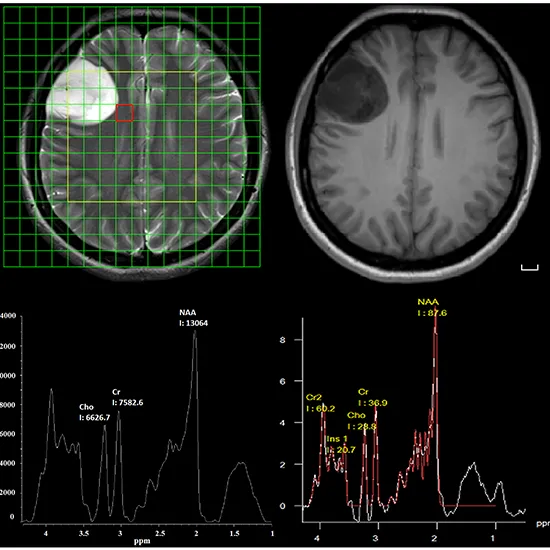

MR Spectroscopy identifies various biochemical changes in the tissues. The scan is helpful in the prediction of the grade of gliomas, infection, ischemia, infarction, hepatic encephalopathy, and several mitochondrial disorders.